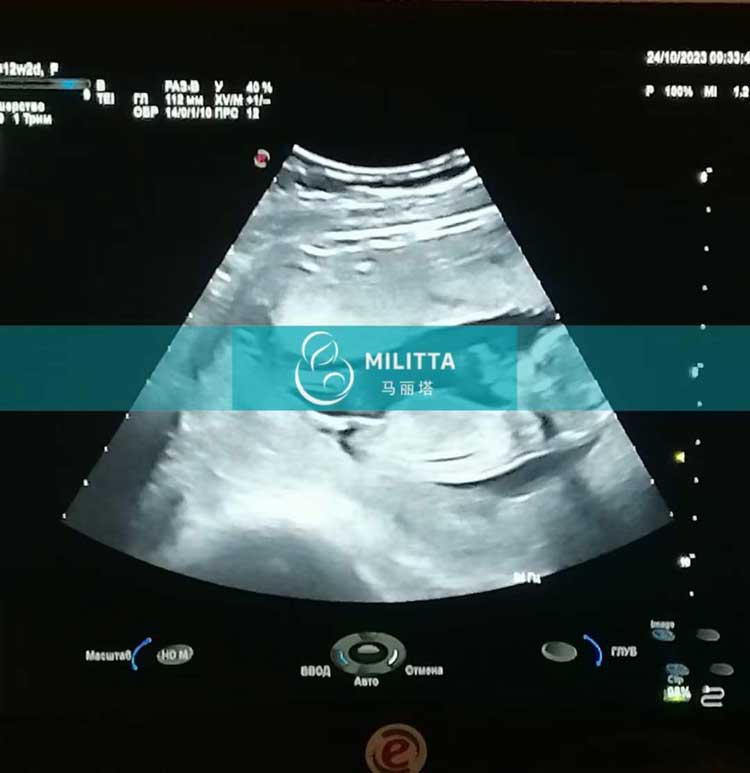

乌克兰试管妈妈来做孕12周的B超,NT检查发育正常

陪同这位乌克兰试管妈妈来做孕12周的B超,B超检查和NT检查都显示发育一切正常,宝宝已经胎稳咯~